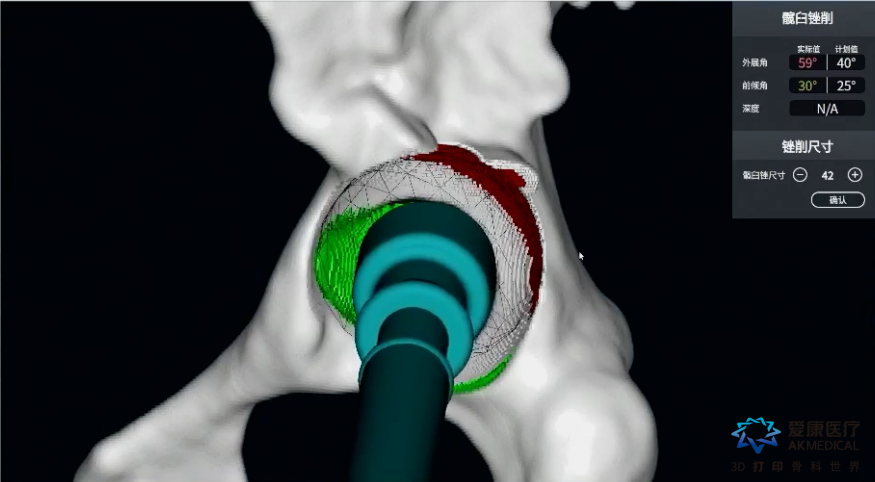

VTS系统辅助磨削